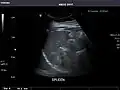

Ultrasound can also be used if there is suspicion of enlargement of one or more organs, such as used in screening for abdominal aortic aneurysm, investigation for splenomegaly or urinary retention.

In cases of infectious mononucleosis, splenomegaly is a common symptom, and health care providers may consider using abdominal ultrasonography to get insight into a person's condition.[5] However, because spleen size varies greatly, ultrasonography is not a valid technique for assessing spleen enlargement and should not be used in typical circumstances or to make routine decisions about fitness for playing sports.[5]

Spleen: Normal in size.